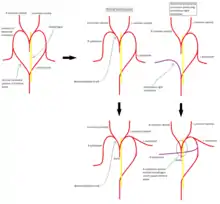

Pathophysiology

In the normal embryological development of the aortic arches, the right dorsal aorta regresses caudal to the origin of the 7th intersegmental artery which gives rise to the right subclavian artery. In formation of an aberrant right subclavian artery, the regression occurs instead between the 7th intersegmental artery and the right common carotid so that the right subclavian artery is then connected to the left dorsal aorta via the part of the right dorsal aorta which normally regresses. During growth, the origin of the right subclavian artery migrates until it is just distal to that of the left subclavian.[3]